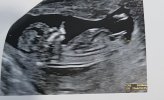

My już po .

Mała ma wsztstko na swoim miejscu , z pappa ryzyko bardzo niskie .

I mogę malować pokój na różowo.

Twierdzi że baba jak nic

Załączniki

• 20201231_135540.jpg

20201231_135540.jpg

533,8 KB · Wyświetleń: 87